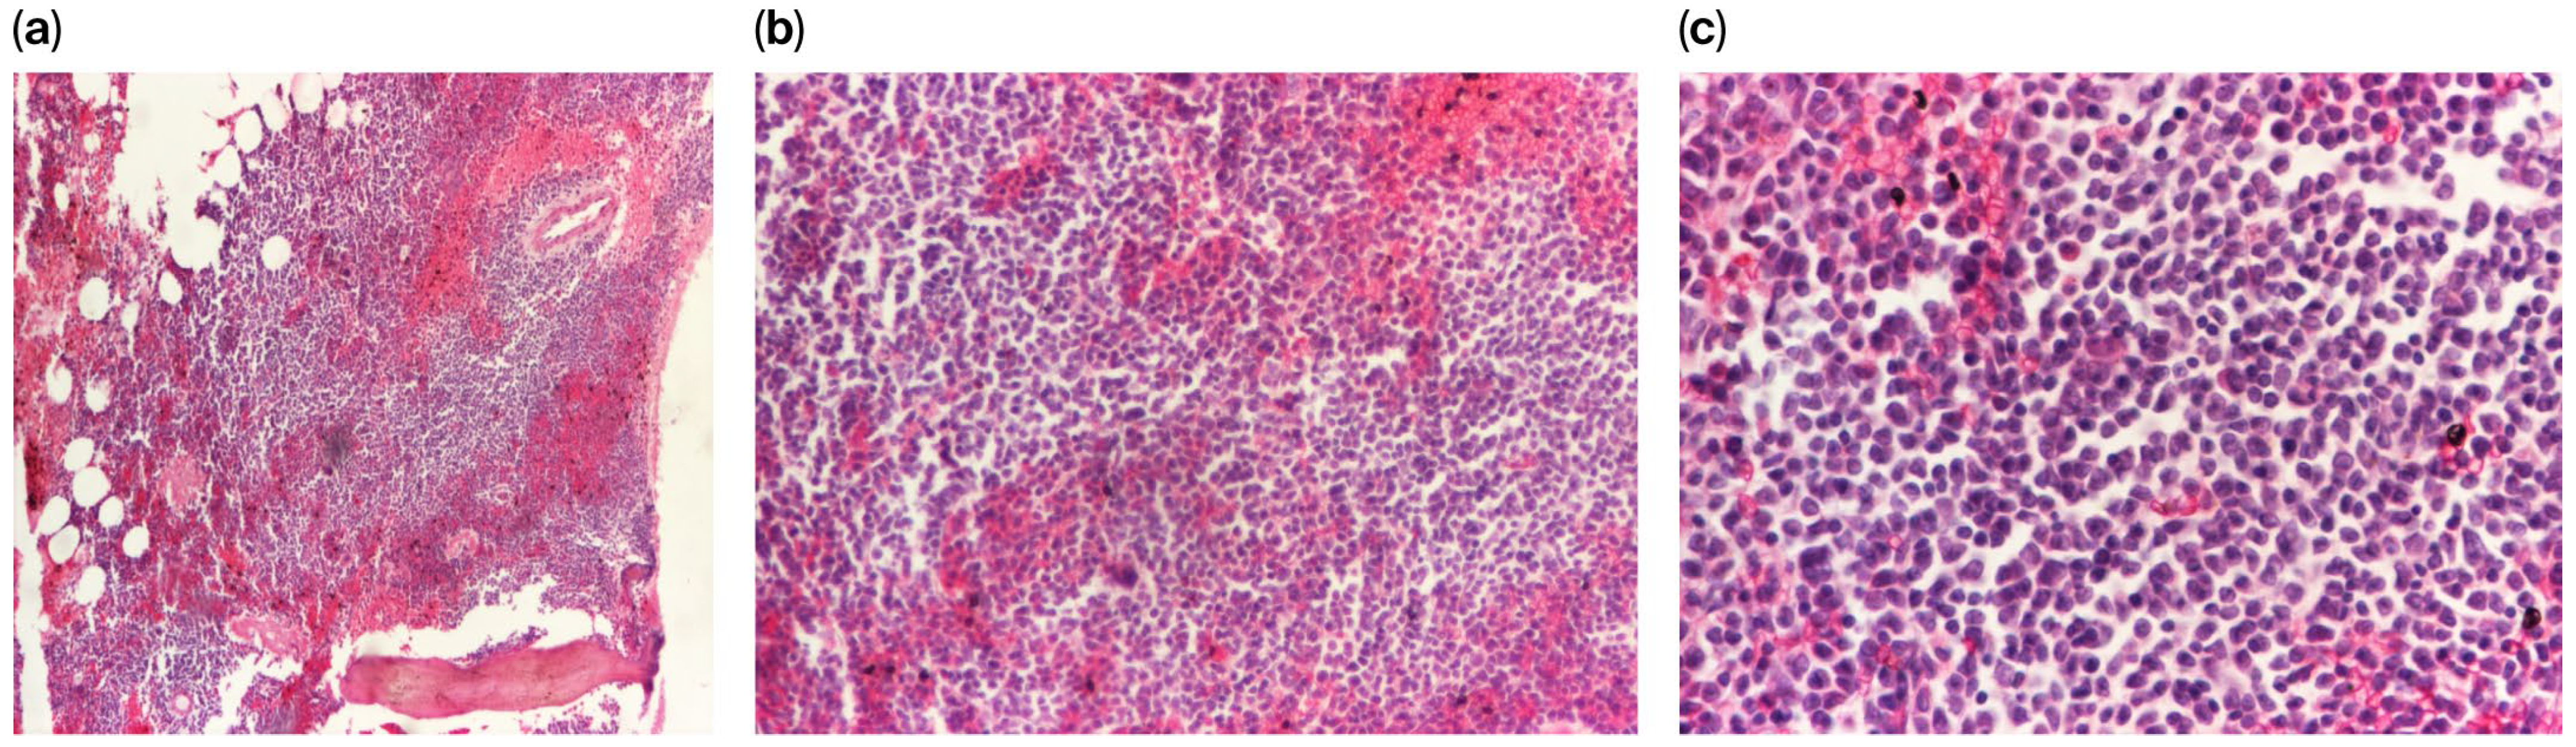

The bone marrow aspirate demonstrated a hypercellular marrow characterized by 43% blast cells. These blasts were medium-to-large and exhibited a high nucleocytoplasmic ratio, frequently presenting lobulated or indented nuclei with one to three visible nucleoli and weakly basophilic, agranular cytoplasm. The granulocytic series was quantitatively reduced to approximately 25%, consisting primarily of myelocytes and mature granulocytes, while the megakaryocytic series remained normoplastic with evidence of active thrombopoiesis.

Cytochemical analysis demonstrated that 38% of the blast population was PAS-positive, exhibiting a fine granular pattern with a calculated glycogen score of 0.8. The myeloperoxidase reaction, performed using ortho-toluidine, identified peroxidase positivity in 22% of the blasts.

Based on these findings, the bone marrow presented features consistent with acute leukemia. Given the cytochemical profile, the differential diagnosis included MPAL Myeloid/B-cell, NOS according to the WHO 2008 classification. Alternatively, considering the presence of the voluminous mediastinal mass, these findings could suggest bone marrow involvement in the context of a myeloid sarcoma with associated biphenotypic myeloid–lymphoid acute leukemia (Figure 2).

Figure 4. (ac) Histopathological assessment of the bone marrow biopsy at varying magnifications (40×, 100×, and 200×) using hematoxylin and eosin (H&E) staining.